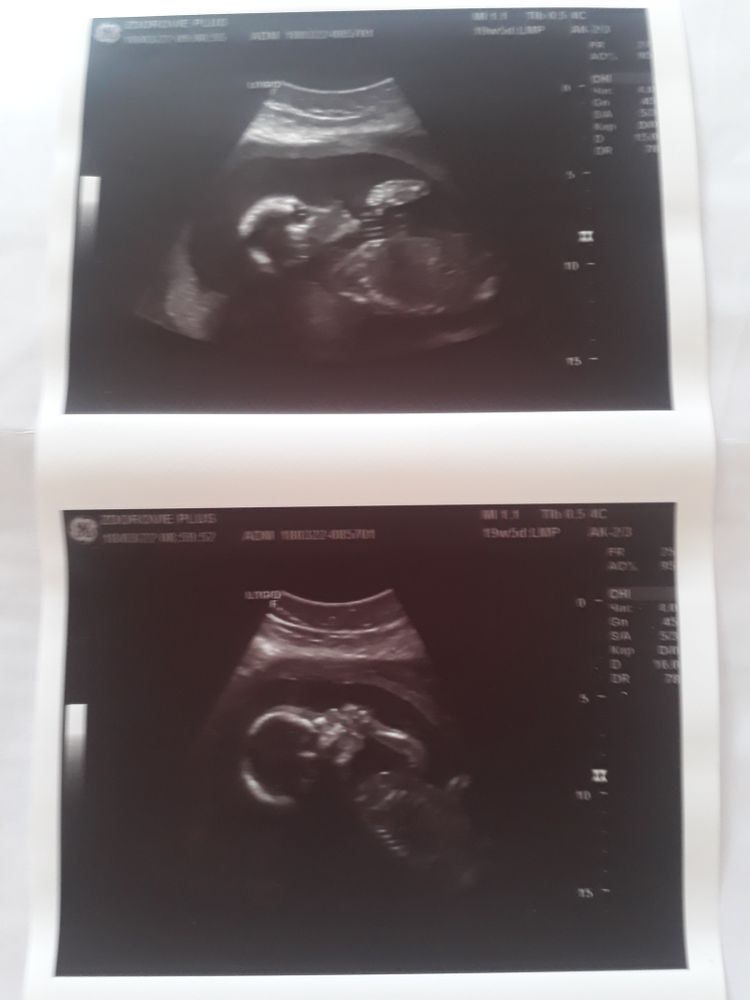

Девочки, всем привет! Сегодня были на втором скрининге. Срок 19+5(По узи 21+2), сыночек вел себя спокойно, дал все померить. Он у нас вообще спокойный ребетенок, шевелиться мало, но активно. Вес 358 гр, сердцебиение 138 уд/м. Будет высокий и худой как папа, длинноногий он у нас.